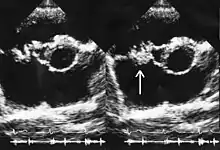

Infections of the central nervous system

In animal studies of meningitis caused by Streptococcus pneumoniae, linezolid was found to penetrate well into cerebrospinal fluid, but its effectiveness was inferior to that of other antibiotics.[52][53] There does not appear to be enough high-quality evidence to support the routine use of linezolid to treat bacterial meningitis. Nonetheless, it has been used successfully in many cases of central nervous system infection—including meningitis—caused by susceptible bacteria, and has also been suggested as a reasonable choice for this indication when treatment options are limited or when other antibiotics have failed.[54][55] The guidelines of the Infectious Diseases Society of America recommend linezolid as the first-line drug of choice for VRE meningitis, and as an alternative to vancomycin for MRSA meningitis.[56] Linezolid appears superior to vancomycin in treating community-acquired MRSA infections of the central nervous system, although very few cases of such infections have been published (as of 2009).[57]